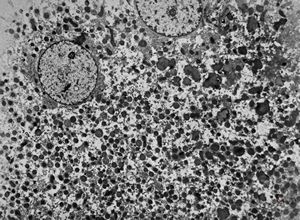

M,1y. | glycogenosis type I.(glycogen dissolved due to UA blockstaining)

F,1y. | glycogenosis type II.(glycogen dissolved due to UA blockstaining)

F,1y. | glycogenosis type II. (glycogen dissolved due to UA blockstaining)